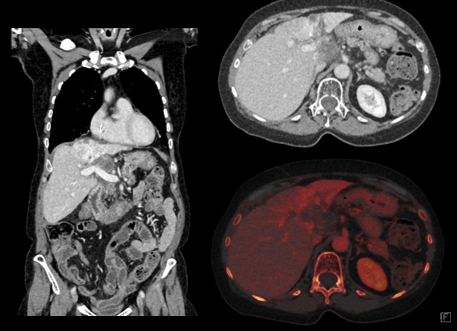

다음과 같은 검사가 가능합니다.

* 이해를 돕기 위한 이미지이며, 실제 촬영 시 이와 상이할 수 있습니다.